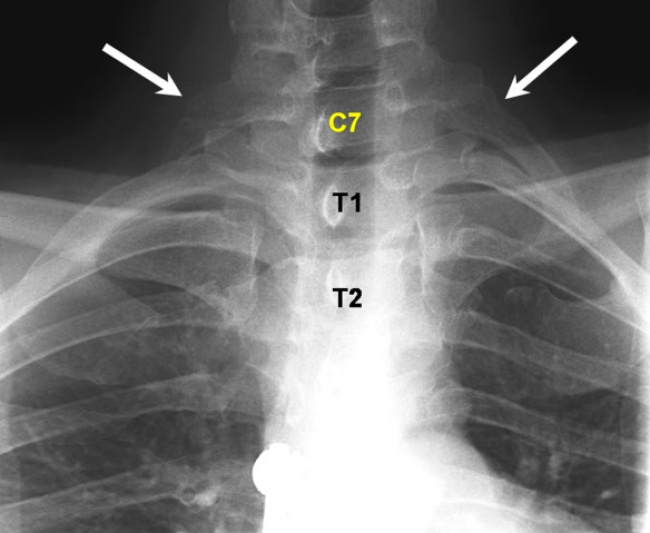

Додаткові ребра

«Зайві» ребра частіше виявляються у прекрасної половини людства. Мабуть, з цієї причини деякі люди вірять, що жінки народжуються з великою кількістю ребер, ніж чоловіки, але насправді це не так.

Такі ребра ще називають шийними, так як вони локалізуються в шийному відділі хребта. Їх розміри у різних людей неоднакові — у кого-то вони являють собою невеликі нарости, в той час як у інших є повноцінними ребрами.

Ці ребра в більшості випадків ніяк не впливають на здоров'я і самопочуття людини, але часом вони досягають значних розмірів і можуть заподіювати дискомфорт.

Джерело: patient.info